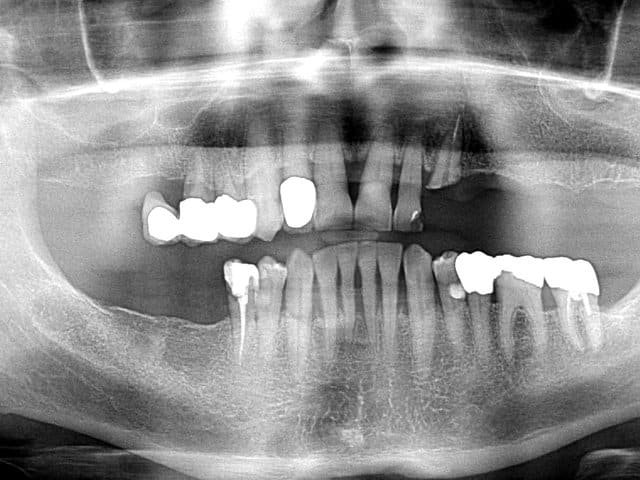

Pour ceux que ca interessent, et parce qu on a m a demandé des cas supplémentaires dans le sujet 23 implants rehabilitation totale, voici un autre cas d implantation immédiate avec la technique minimalement invasive et condensation grace aux forets.

Le patient a reçu un traitement il y a dix ans dans le maxillaire et dans le 4eme quadrant.Comme on peut le voir j´ai du extraire quelques dents au maxillaire: 35 37 et 45.

Le septum de la 37 a été foré avec un foret conique 3 faces.

J ai planté à 60 Ncm sans fracturer le septum.Juste après l opération , les prep caps en zircon ont été cémenté.La restauration définitive 34 jusqu` à 37 été fixé 2 semaines après l implantation avec implantlink (detax). Après un an, le bridge a été retiré facilement pour voir l´état de la gencive et faire une radio de contrôle.On la re ossifiction est satisfaisante et que la gencive "aime" le zircon.

Le bridge a ensuite été recémenté sans correction nécessaire du bridge.